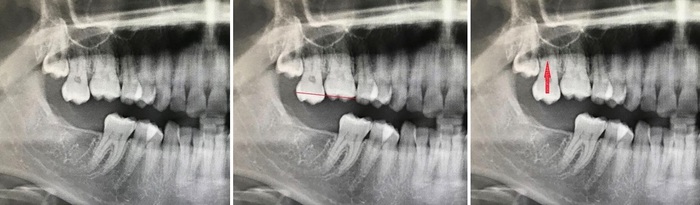

Открываю я снимок и вижу, что действительно так и было:

Черная полоска, уходящая в правый нижний угол картинки, отмеченная кружком, и есть то место, где был перебит нерв.

Я сказал Константину, что никаких проблем удалении не вижу, тем более все осложнения, которые могли быть, он уже хапнул.